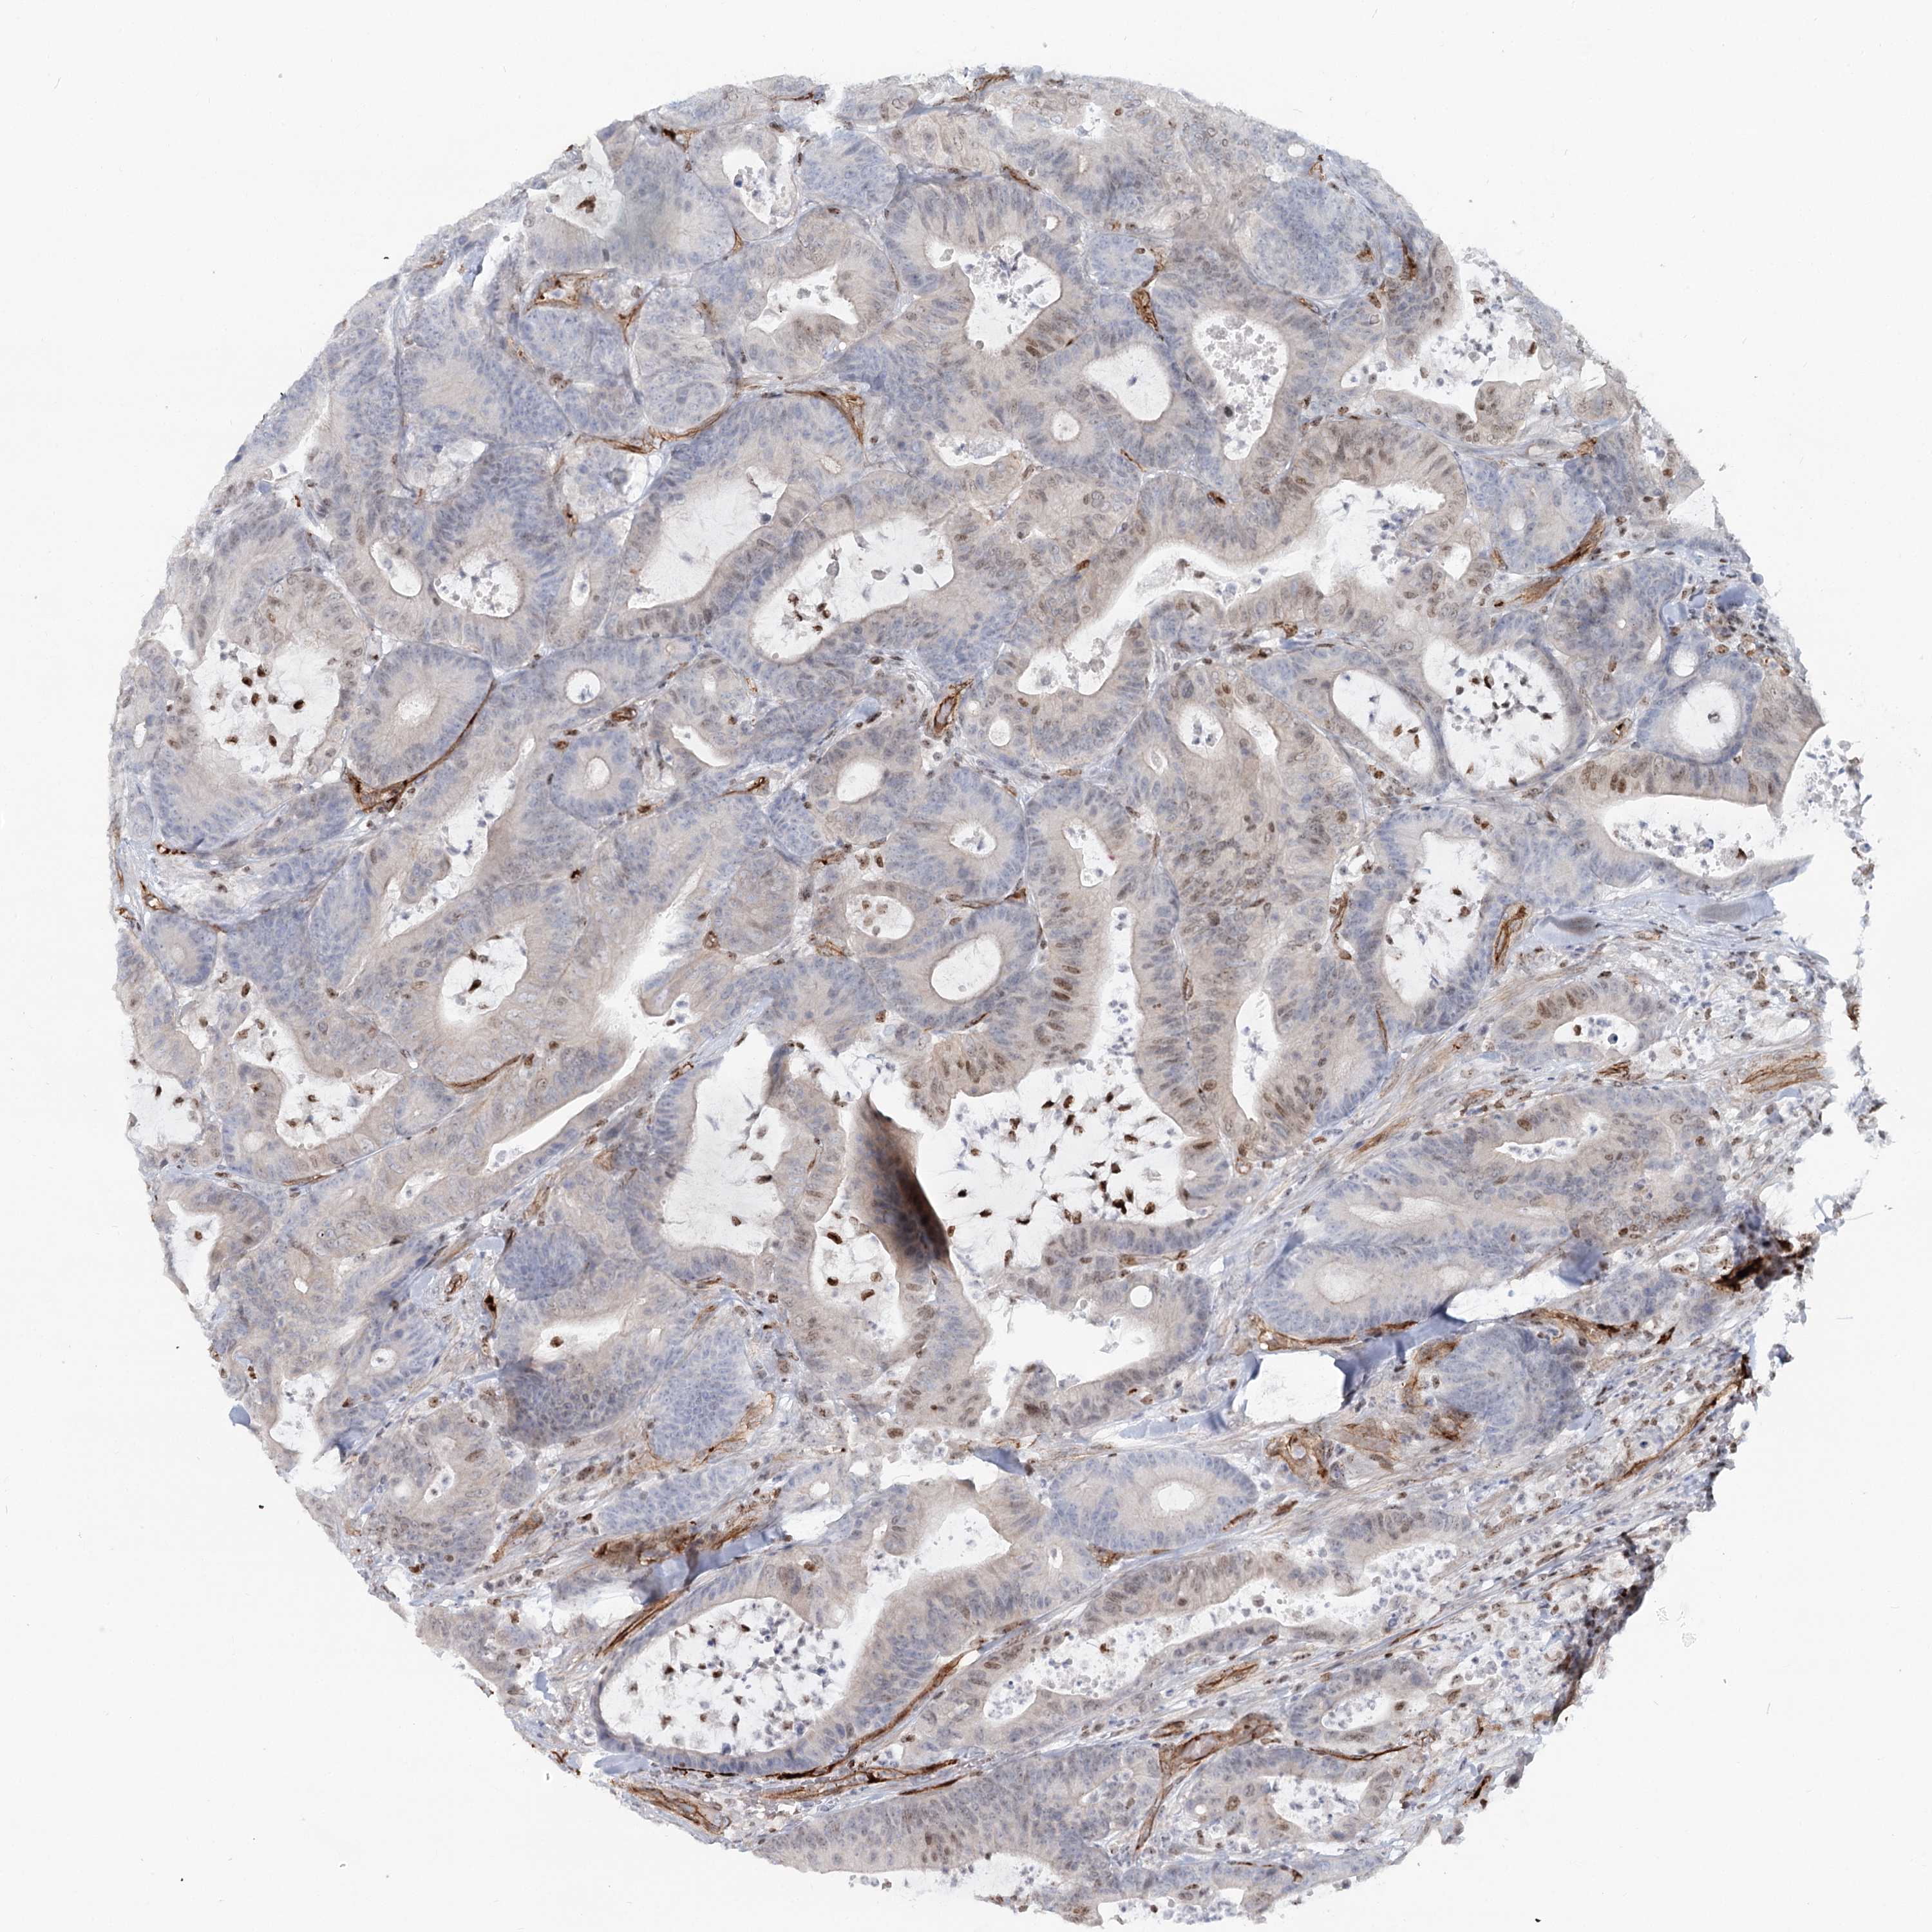

Colorectal cancer

Colon adenocarcinoma